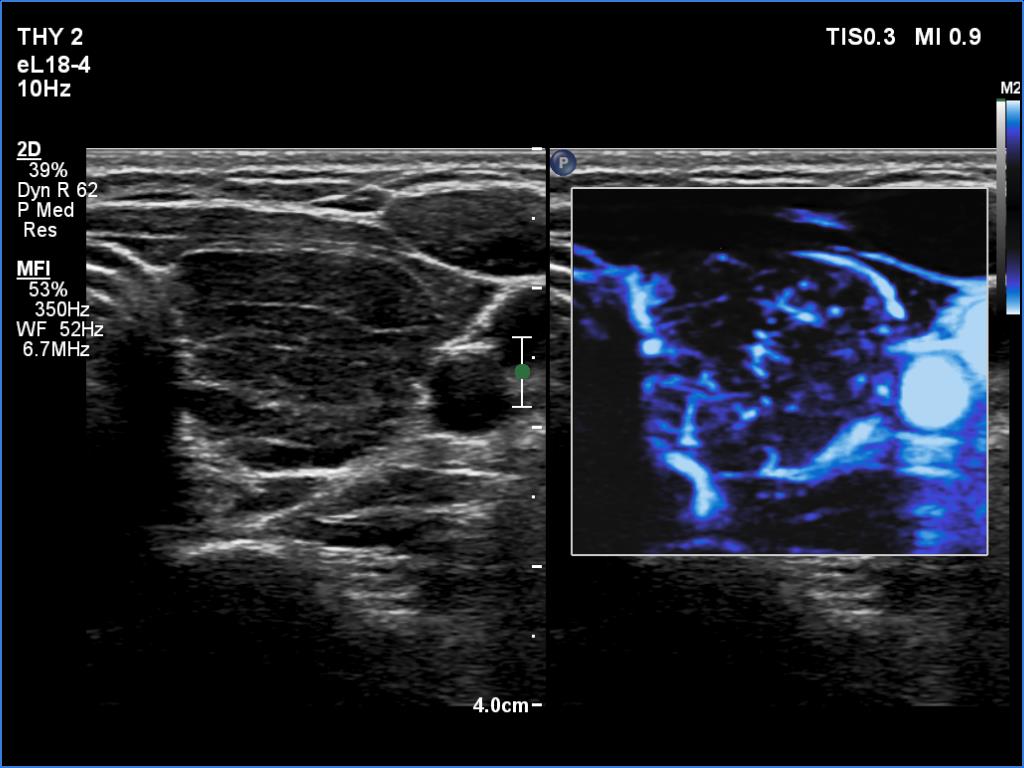

Right lobe, longitudinal scan

Left lobe, transverse scan, microflow imaging. The vascularity is average.